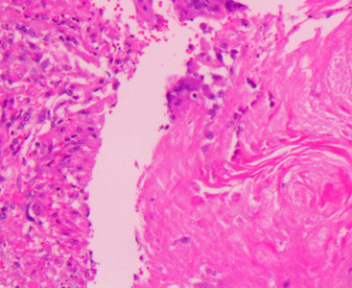

上臂肿物

标本名称

大体所见

灰白不规则软组织1块1.5x1.5x1cm。

图3